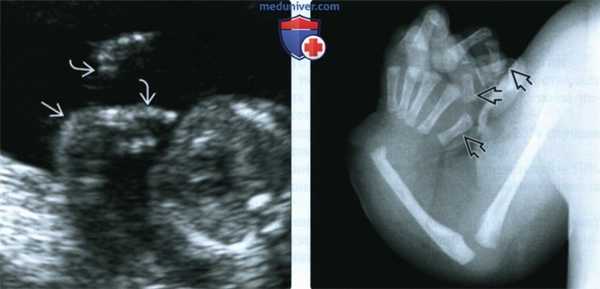

(Слева) УЗИ плода в 19 нед. Синдром Холт-Орама. На кисти определяются 4 пальца, I палец отсутствует. Отмечается клинодактилия V пальца.

(Справа) Тот же случай. Клиническая фотография кисти новорожденного. Медиальная девиация кисти обусловлена отсутствием лучевой кости Кроме того, плечевая и локтевая кости гипоплазированы. I палец отсутствует, присутствуют только 4 пальца. Клинодактилия V пальца совпадает с более ранней находкой по УЗИ. (Слева) УЗИ плода во II триместре. Синдром Холт-Орама. Определяется дефект радиального луча: лучевая кость гипоплазирована, кисть медиально отклонена. Изначально по результатам пренатальной лучевой диагностики предполагалось отсутствие I пальца кисти, однако после рождения ребенка установлена гипоплазия пальца.

(Справа) Четырехкамерный срез сердца плода в III триместре. Визуализируется небольшой ДМЖП. Самым частым пороком сердца, встречающимся при синдроме Холт-Орама, является ДМПП, обнаружить который до родов особенно сложно. (Слева) УЗИ верхней конечности плода в 26 нед. Синдром Холт-Орама. Отмечаются выраженная гипоплазия лучевой кости медиальная девиация кисти и олигодактилия. I палец отсутствует.

(Слева) УЗИ кисти плода в конце I триместра. Синдром Холт-Орама, дефект радиального луча верхней конечности. Определяются только 4 пальца, I палец отсутствует.

(Справа) УЗИ плода во II триместре. Синдром Холт-Орама. Отмечаются умеренная гипоплазия лучевой кости, медиальная девиация, а также выраженная гипоплазия кисти. Локтевая кость умеренно искривлена. (Слева) УЗИ плода в 12 нед. Беременная страдает синдромом Холт-Орама. Визуализируются признаки дефекта радиального луча, а также косорукость. Указанные патологические находки, а также отягощенный анамнез матери позволяют заподозрить у плода синдром Холт-Орама.